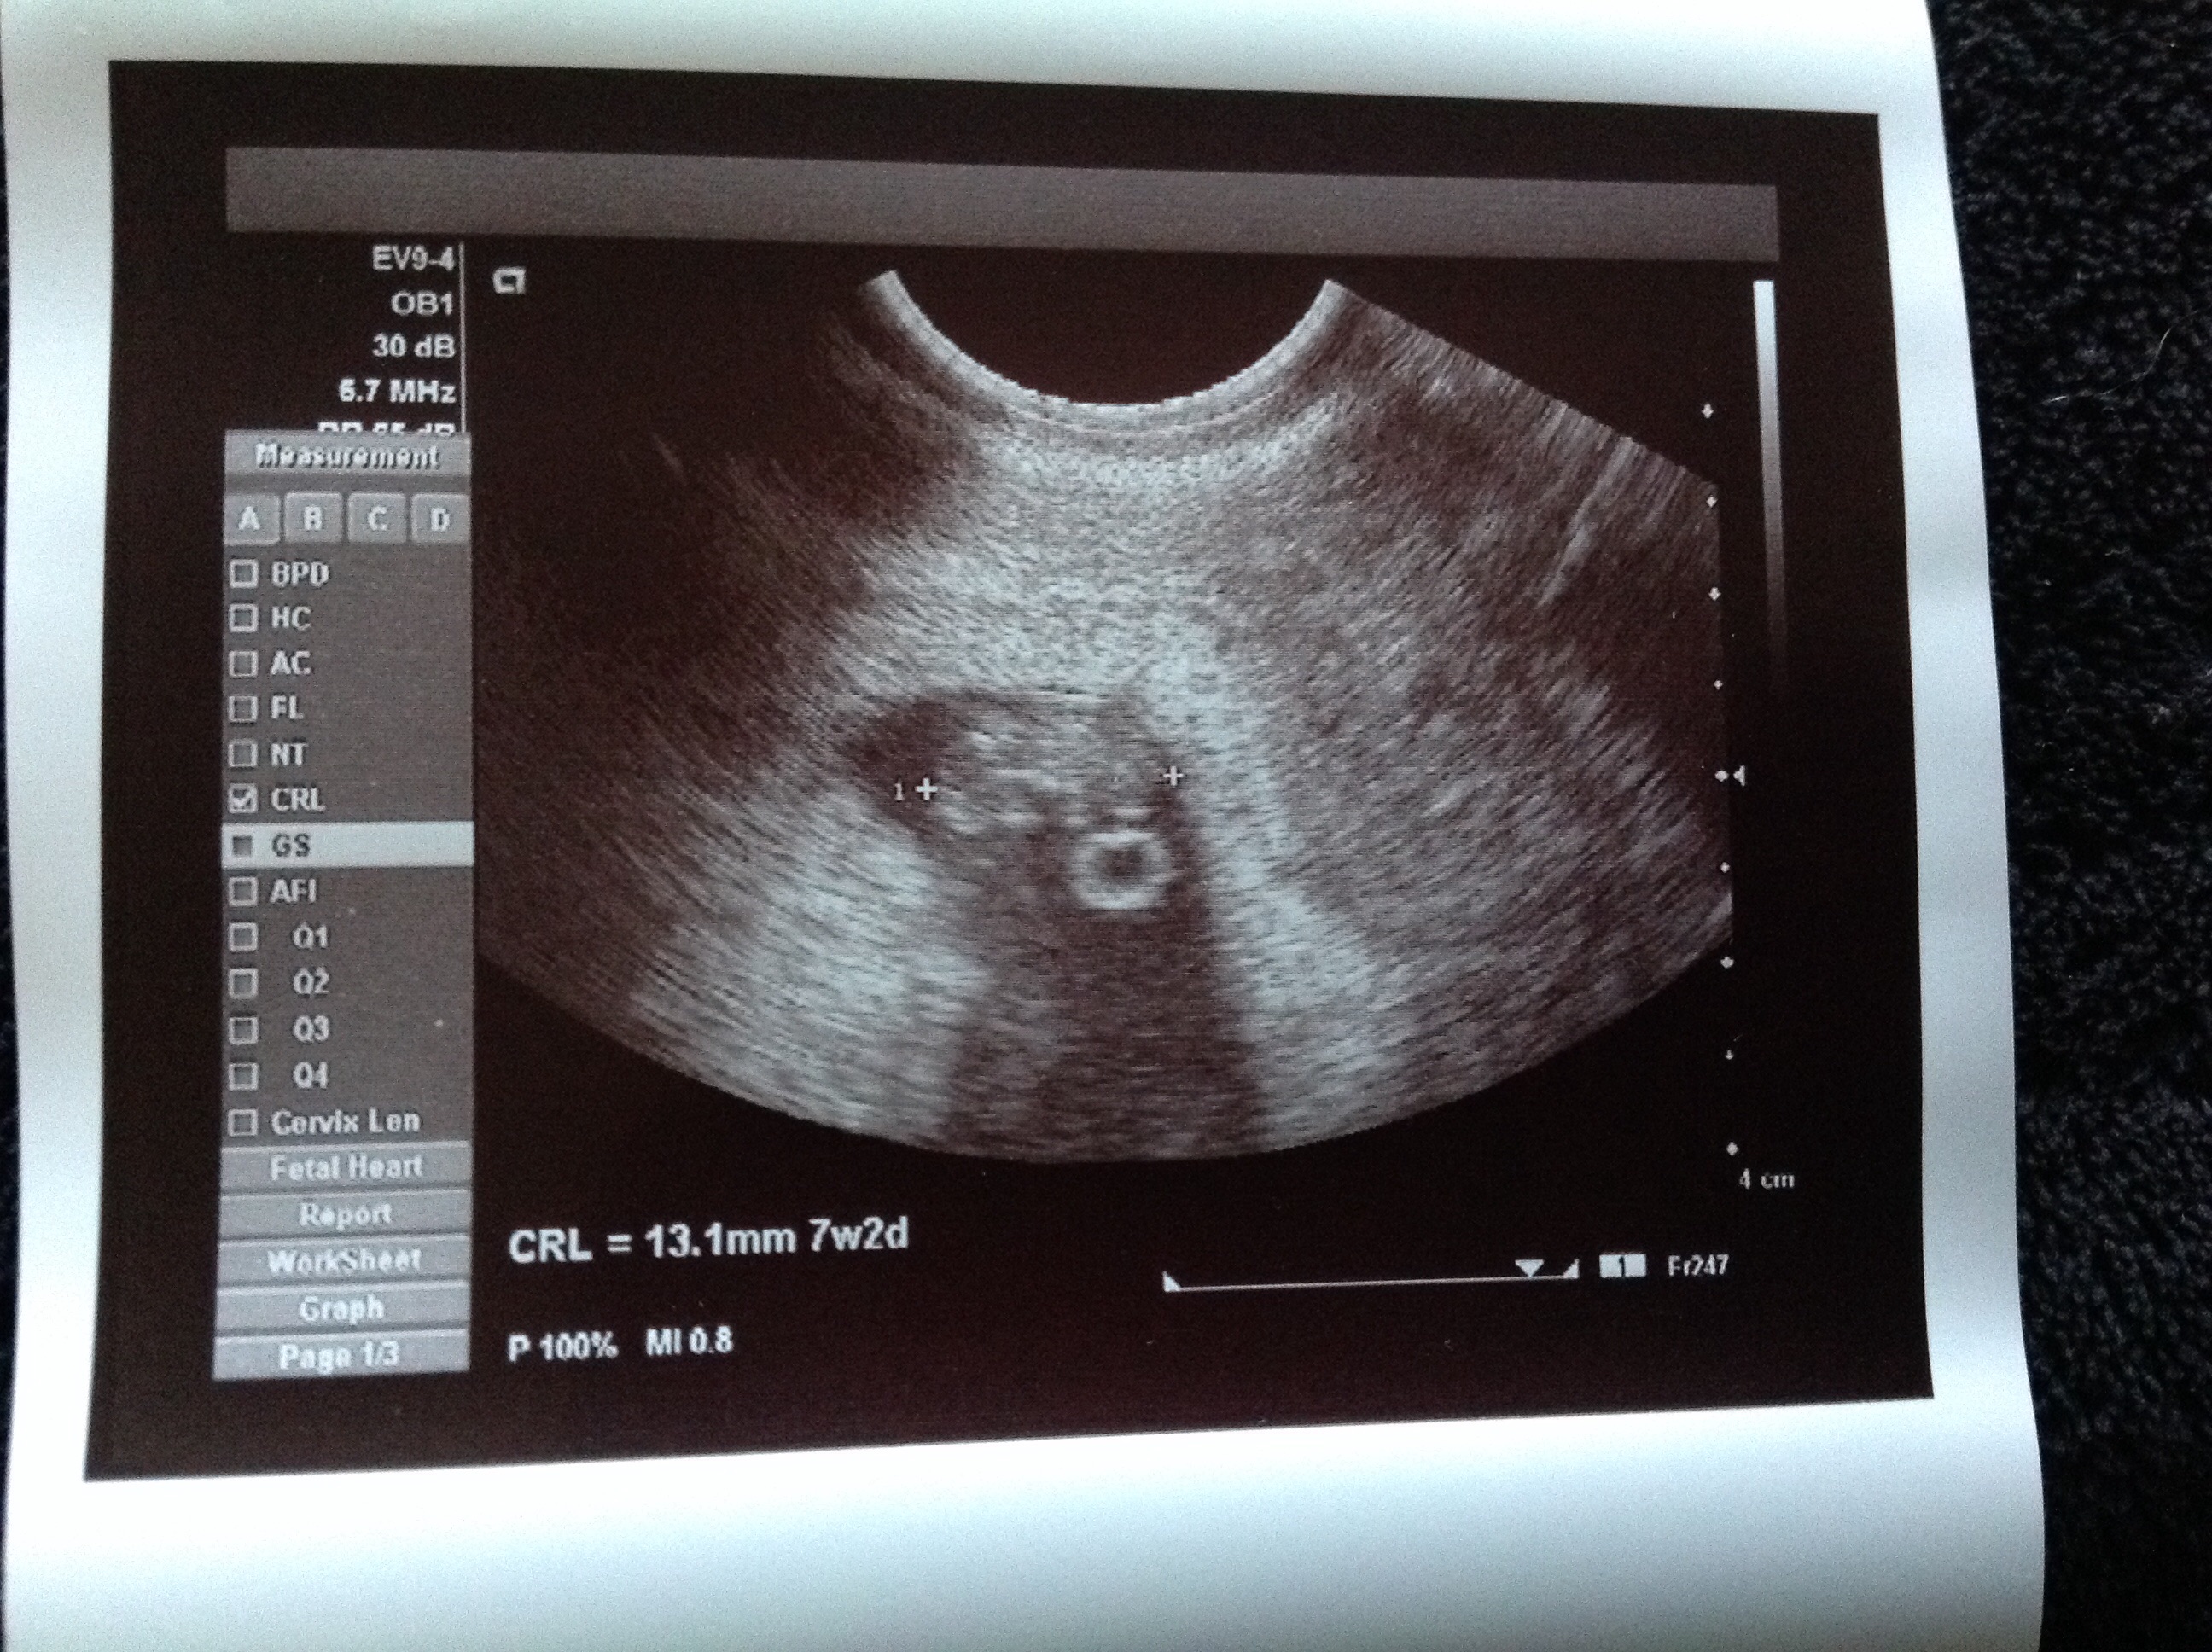

• My little munchkin at 6 weeks and 3 days, it was so small, and so adorable, and I got to hear it's heart beat :)